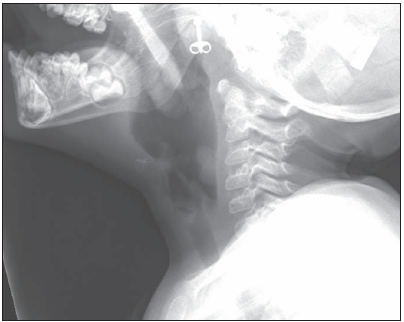

A 27-month-old girl is brought in for evaluation of hoarseness. She was born prematurely, at 27 weeks' gestation, and spent her first 4 months in the neonatal ICU.